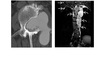

ENCHONDROMA

Commonest location Hands/feet

Long bones: proximal humerus > distal and proximal femur > proximal tibia

Intramedullary and metaphysis

multiple enchondroma

Maffuci - haemangioma

Olliers - multiple enchondroma only

DDx

-Brown tumor (hyperparathyroidism),

-sarcoid - lace like bone lesion phalanges

-intraosseous ganglion

-metastatic disease.

MRI

T1: low to intermediate signal

Fluid-sensitive sequences: lobulated high signal typical of cartilage lesions

Enhancement: peripheral and septal, accentuating lobules

Chondrosarcoma

May be cecondary to

- Osteochondromas

- enchondromas

Chondrosarcomas occur in the pelvis, femur, humerus.

Skull base, TMJ

-Most well differentiated, low grade = ‘low grade chondroid lesion’ , cant differentate from enchondroma

-Bone infarct

Lobular growth

High 2 signal/STIR, low T1

ring and arcs/chondroid matrix islands on CT

Soft tissue extension

**endosteal scalloping. **

if no mineralized matrix/rings and arcs = aggressive/high grade

How to tell chondrosarcoma from enchondroma ?

* Pathological fracture occurring with minimal trauma

* Multilayered or spiculate periosteal reaction

* Permeative or moth-eaten osteolysis

* Cortical destruction

* A soft tissue mass

Endosteal scalloping more than 2/3 cortex